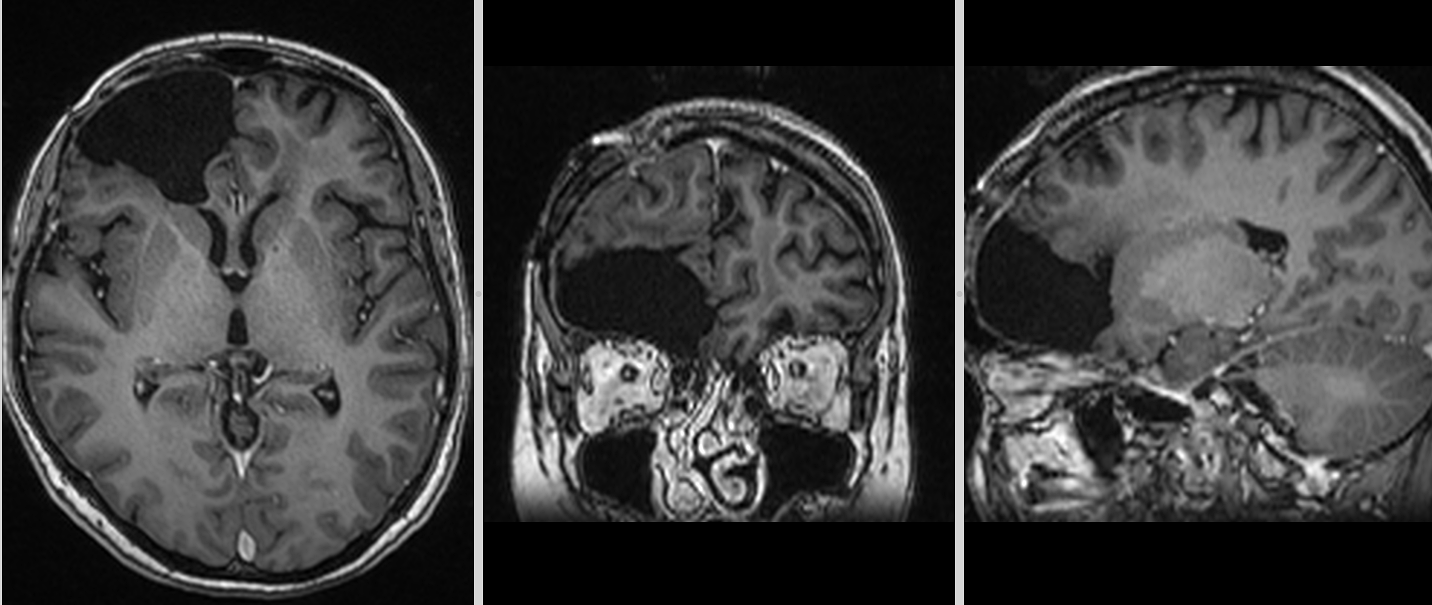

Se reface imagistica – de aceasta dată RMN cerebral cu contrast – și se constată prezența unei tumori cerebrale infiltrative de cca 7/7/6 cm, în cea mai mare parte negadolinofila, hipo-T1, hiper-T2 și FLAIR, cu zone hemoragice la interior și efect de masă important – deplasarea structurilor liniei mediene cu 2 cm, hernie de girus cinguli și hidrocefalie internă prin obstrucția formen Monro – imagine sugestivă pentru un gliom de grad înalt, cel mai probabil glioblastom.

Totuși, la aproximativ 3 ani de la intervenția inițială, RMN-ul cerebral a evidențiat o modificare suspectă la nivelul zonei operate.

Aspectul nu era cel clasic de recidivă agresivă.

Leziunea avea caracteristici mai apropiate de un proces de tip low-grade, cu evoluție lentă și fără semne de agresivitate marcată.